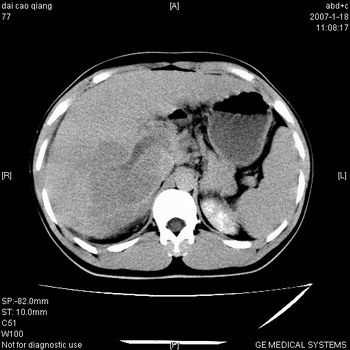

符合巨块型肝癌表现:

1、平扫低密度,增强后表现为快进快出。

4、可见假包膜

5、腹主动脉旁结节影,考虑肿大淋巴结。

肝右叶巨块型肝癌,伴瘤栓形成,肿瘤有包膜,可见动静脉短路。

肝右叶巨大不均匀低密度肿块,前缘有假包膜,增强明显的呈快进快出表现,门脉右支有癌栓,病人虽然年轻但还是首先考虑肝右叶巨块形肝癌,病人血象高只能说有合并感染。不支持肝脓肿。